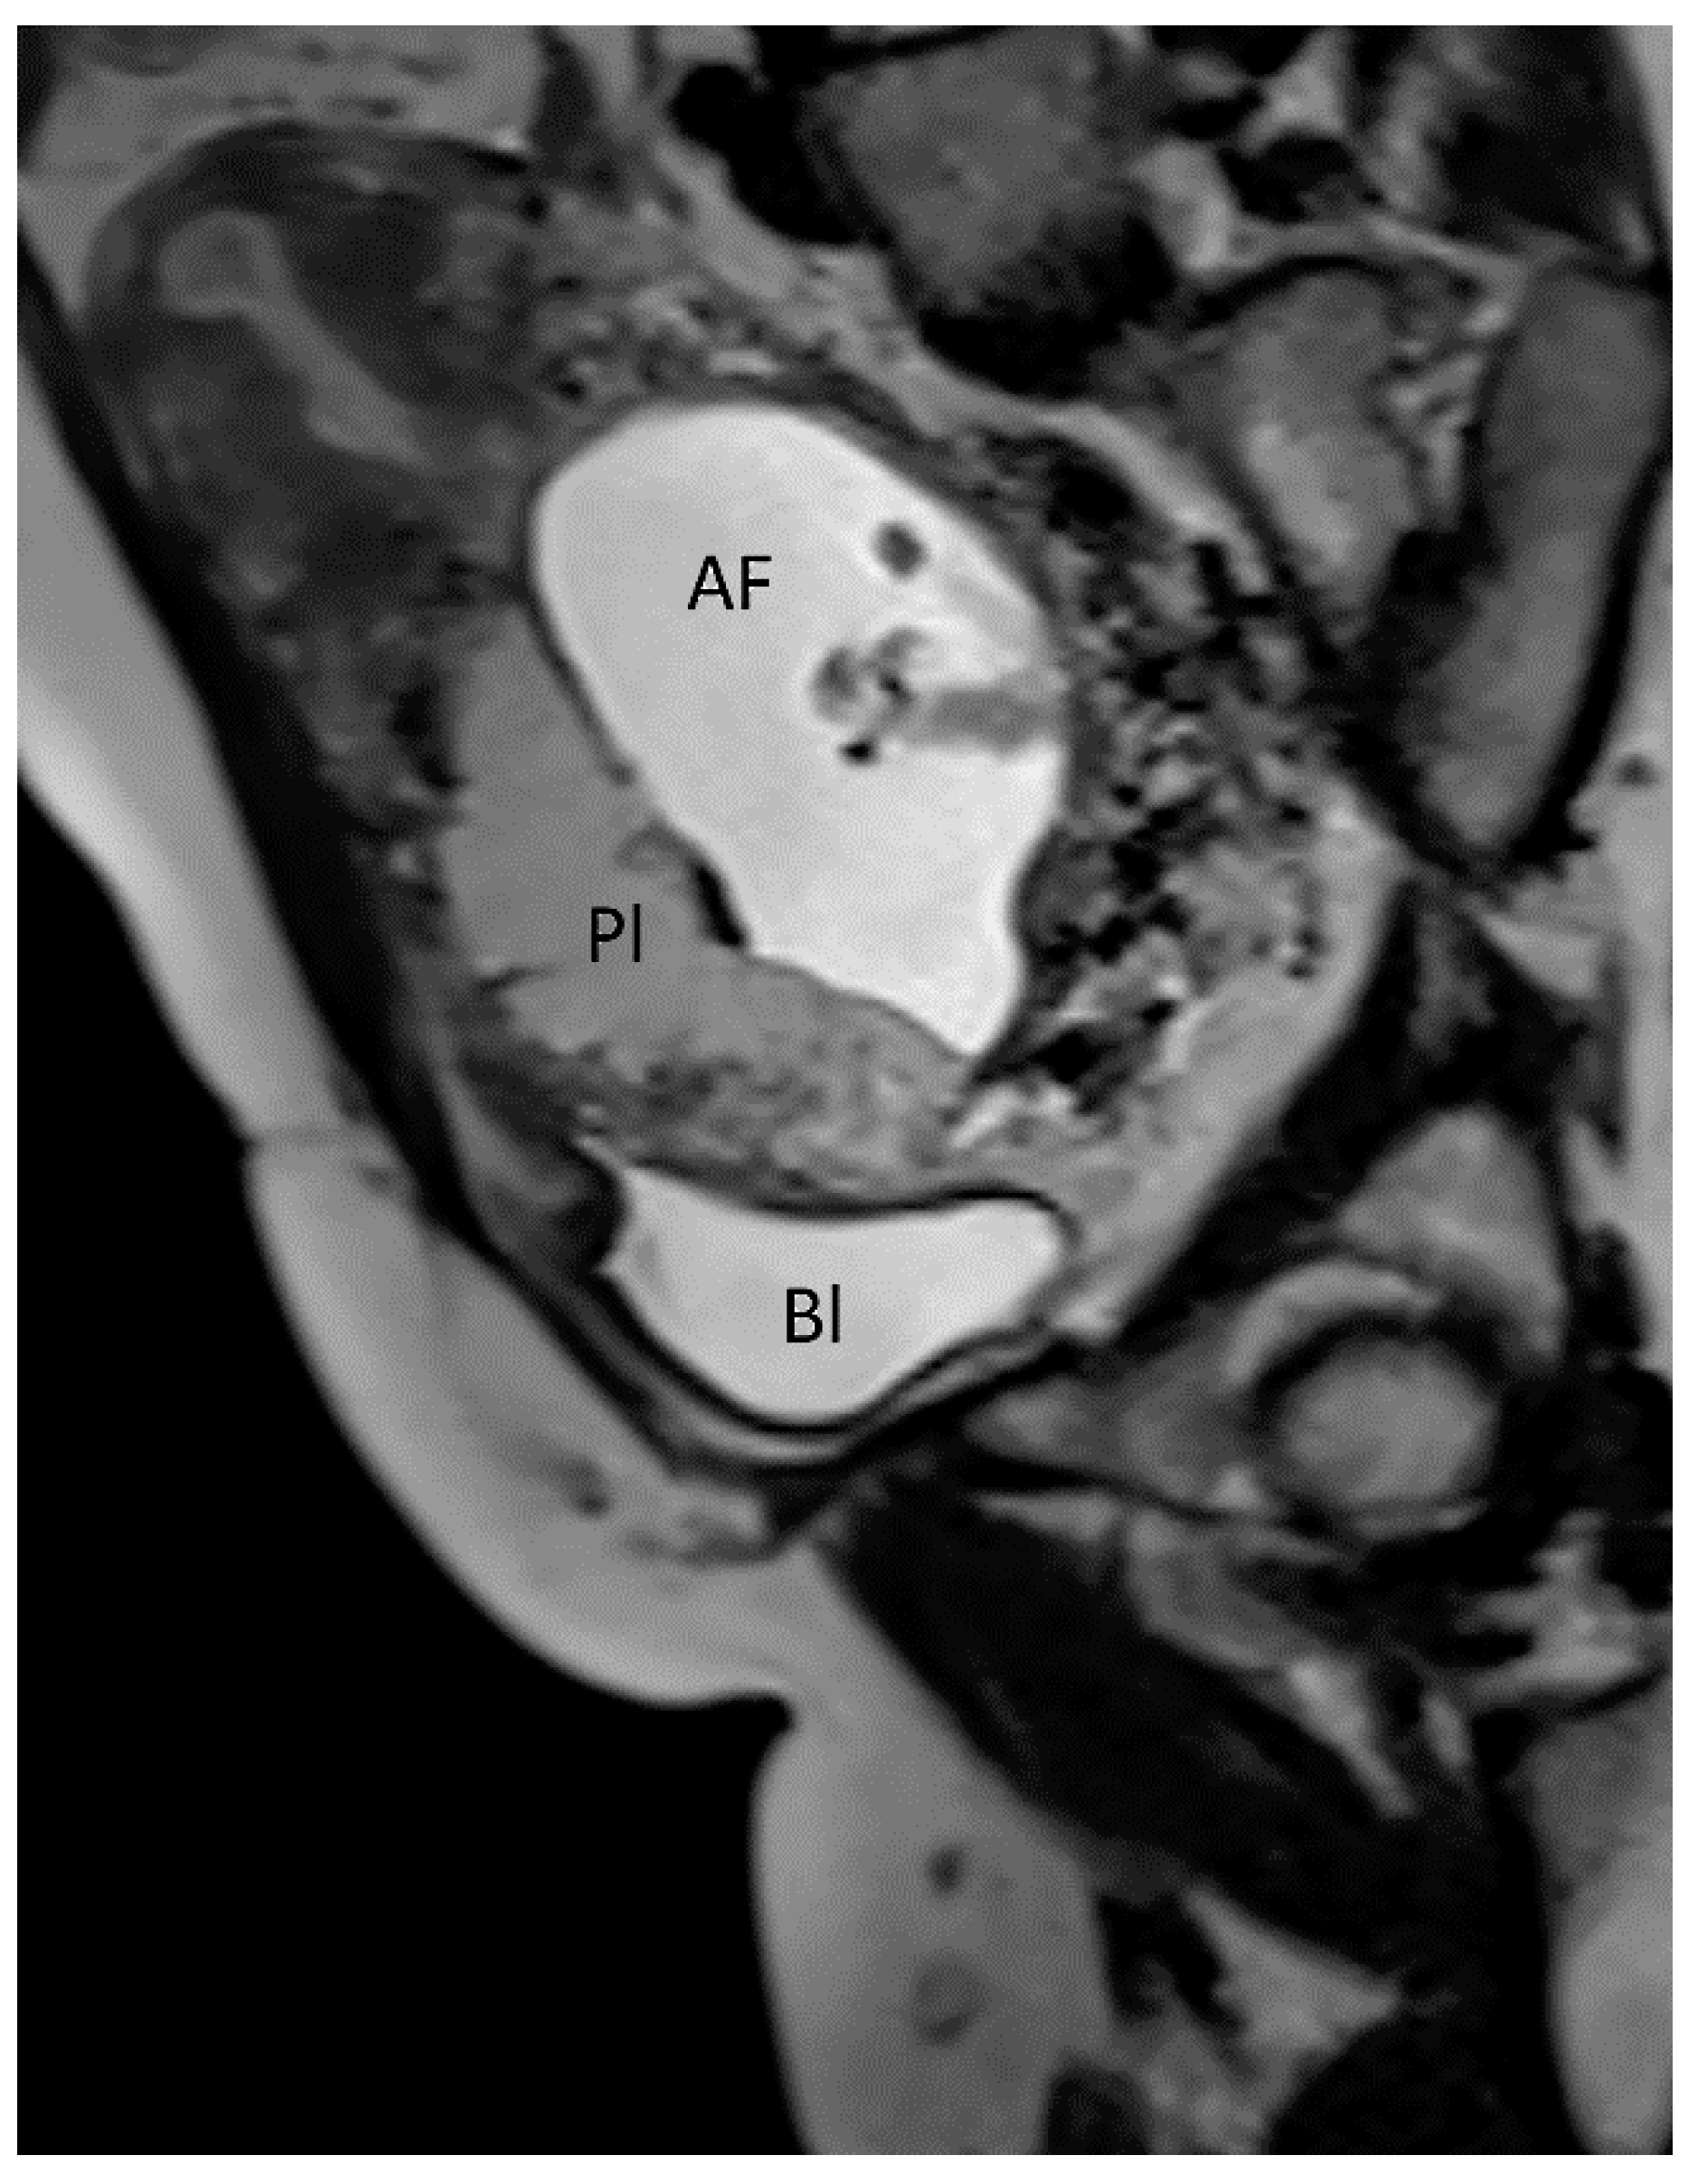

3.1.1. Placenta Accreta Spectrum

3.1.2. Placenta Praevia